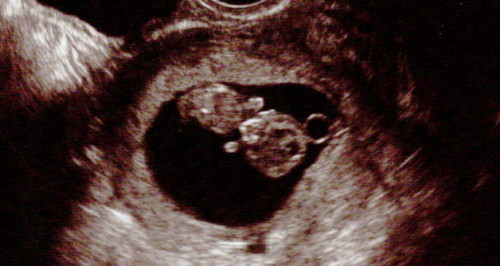

エコー写真を見た。九週目だそう。

ぶどうみたいに丸いのがちょこんと引っ付いてて何だか懐かしい写真だった。嫁曰く小さな心臓がトクトク動いていたらしい。

「これ見ちゃうと何とも言えないね」

嫁はエコー写真を出した。

「見て」

三女の落書き。ちなみに4ヶ月ではない。9週目。